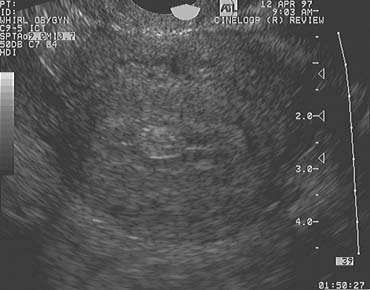

The endometrium undergoes dramatic morphologic changes across the normal menstrual cycle that can be easily and rapidly evaluated by TVUS (Fig. 9).15,16,17,18,19 The endometrium is the principal target of steroid hormones produced by the ovaries and time invested in learning how the two relate is well spent.

Fig. 9. Mid sagittal images of the uterus (A–D). A. Pattern A. The lumen is visualized as a thin hyperechoic line in the middle of the myometrium. The stratum basalis and stratum spongiosum of the endometrium are not seen. This morphology is typically observed immediately following menstruation. B. Pattern B. The lumen is visualized and thin stratum basalis and stratum spongiosum layers are observed superior and inferior to the lumen. This morphology is typically observed in the early to mid- follicular phase. C. Pattern C. Thick hypertrophied endometrium in which the lumen, stratum basalis, and stratum spongiosum are observed. This morphology is typical of the late follicular phase and estrogen exposure. D. Pattern D. This pattern is observed postovulation and is the result of progesterone exposure. The endometrium is homogeneous, the lumen is typically not detected, and distinction between stratum basalis and stratum spongiosum is faint, if observed at all.

The endometrial detail revealed by high-resolution TVUS is striking. The inner and outer strata of the endometrium can be easily identified, and observations of the changes in the echotexture of the intervening stratum spongiosum across the menstrual cycle provide the means to evaluate endometrial growth and development.19 Variations in the appearance of the endometrial stripe correlate with the cyclic patterns of circulating estrogen and progesterone and thus represent a bioassay of their actions. During the proliferative phase of the endometrial cycle (corresponding to the follicular phase of the ovarian cycle), when estrogen concentrations are rising progressively, the hypoechoic stratum functionale grows in thickness to yield a prominent triple-line or trilaminar configuration. After ovulation, the endometrium may thicken further and increases in echodensity. The patterns of ovarian follicular and corpus luteum development should be synchronous with the patterns of endometrial growth and maturation. Discordant patterns suggest the possibility of an abnormality in hormone production or action.